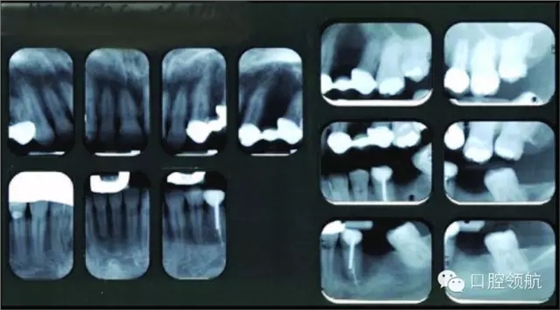

● 未見(jiàn)明顯的松動(dòng)度或者創(chuàng)傷牙合(圖3)。

圖3 上頜左側(cè)后牙的影像學(xué)檢查。